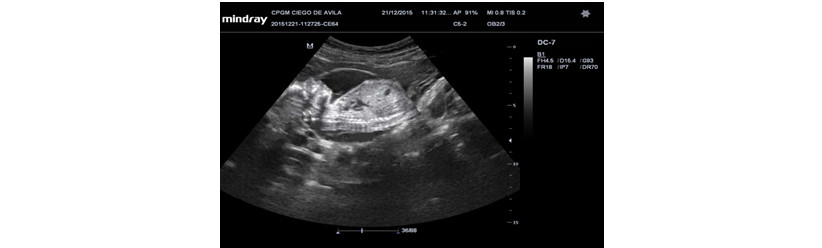

Volver a los detalles del artículo Marcadores ecográficos en la detección del síndrome de Down